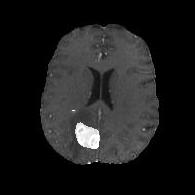

(a) (b) (c) (d)

Boundary Stream:

Fig. 2 demonstrates the output of each of the attention layers in our dedicated boundary stream. In essence, each attention layer progressively localizes the tumor and refines the boundaries. The first attention layer has learned rough estimate of the boundaries around the tumor and localized it, whereas the second and third layers have learned more fine-grained details of the edges and boundaries, refining the localization. Moreover, since our architecture leverages a dilated spatial pyramid pooling to merge the learned feature maps of the regular segmentation stream and the boundary stream, multiscale regional and boundary information have been preserved and fused properly, which has enabled our network to capture the small structural details of the tumor.

(a) (b) (c) (d) (e)

Comparison to Competing Methods:

We have compared the performance of our model against the most popular deep learning-based semantic segmentation networks, U-Net [9] and V-Net [7] (Fig. 3). Our model outperforms both by a considerable margin in all evaluation metrics. In particular, U-Net performs poorly in most cases due to the high false positive of its segmentation predictions, as well as the imprecision of its boundaries. The powerful residual block in the V-Net architecture seems to alleviate these issues to some extent, but V-Net also fails to produce high-quality boundary predictions. The emphasis of learning useful edge-related information during the training of our network appears to effectively regularize the network such that boundary accuracy is improved.